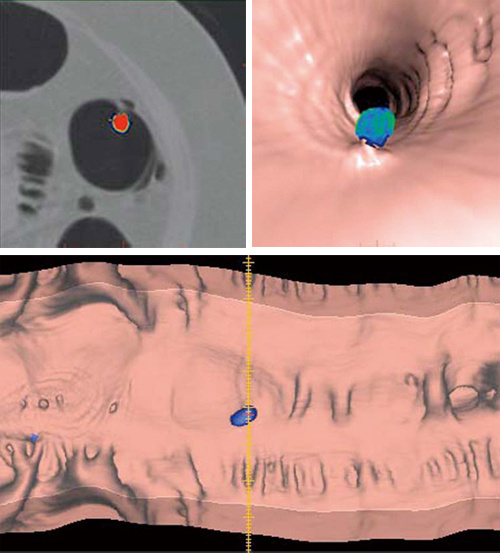

CTCは,直径6mm以上の隆起病変に関しては大腸内視鏡検査とほぼ同等の検出能であると実証されている3)。しかしながら,検出率と読影時間は経験数により左右されるため,見落とし軽減と読影時間の短縮が望まれている4)。それを補うのが,コンピュータ診断支援システムであると言われている。Colon VCAR ECは,隆起性の球体に色付けをするDCA(Digital Contrast Agent)機能を有し,読影医へ注意を促しポリープ検出をサポートする(図3)。

図3 VCAR(Volume Computer Assisted Reading)機能

CTC解析は,病変と残渣,大腸襞を見分けながら,病変のみを的確に把握するのに時間を要した。

しかし,DCA機能は隆起病変に自動で色付けをすることで,直感的に読影者に情報を提供する。今後,読影者の負担軽減へつながる機能として臨床応用が期待される。